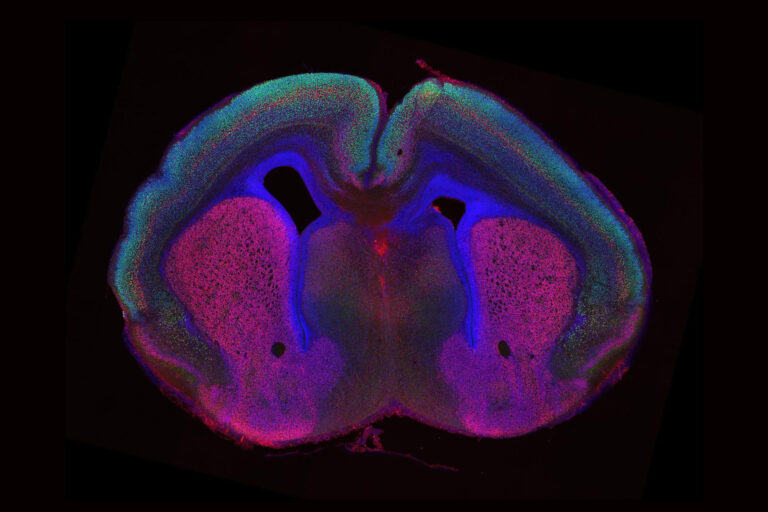

Sprache, Erinnerungen, Kreativität – all das verdanken wir der besonderen Architektur unseres Gehirns. Wer einmal Bilder eines menschlichen Gehirns gesehen...